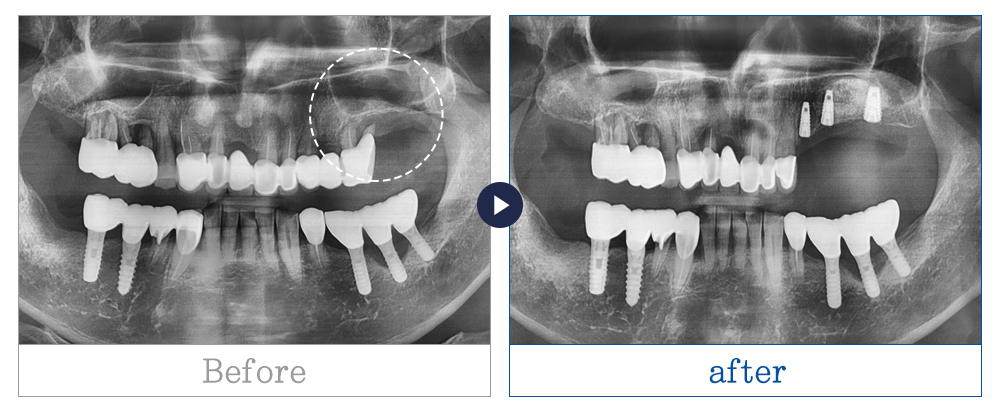

임플란트 사례

치료기간 5개월 이상

* 환자의 상황, 상태, 치료 계획마다 치료 기간은 상이할 수 있습니다